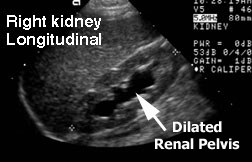

This longitudinal ultrasound shows a kidney with less severe hydronephrosis. The parenchyma is relatively normal in thickness. The dilation of the collecting system extends from the renal pelvis to the calyces. This is a grade III hydronephrosis.